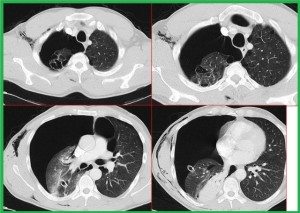

Toraks BT: kesin tanı koydurucu bir yöntemdir. Daha duyarlıdır. Blebleri gösterir, PSP’lilerin %89’unda vardır. Plevral efüzyon pnömotoraksların %10-20’sinde gelişebilir.

Tanı: PA AC grafisinde visseral plevranın görülmesi ile tanı konur. Dev bül – pnömotoraks; klinik ipucudur, pnömotoraks kliniğinde ani dramatik bozulma vardır. Dev bül kronik olduğu için ani gelişen sıkıntılar olmayacaktır. Grafide visseral plevra sınırı belli olmaz, pozisyonla yer değişirmez, sıkışan akciğer hattının açıklığı dışa bakar. Toraks BT kesin tanıda yardımcıdır.